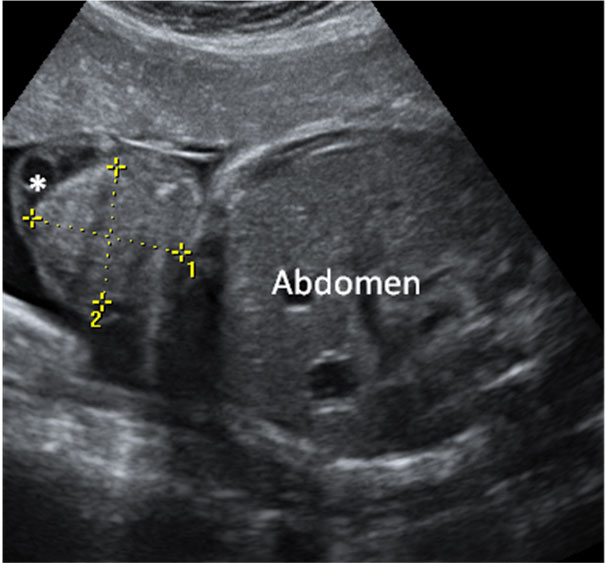

En la ecografía en 2D de la semana 20 de embarazo se hace un estudio pormenorizado de los órganos internos del feto y de su anatomía. Así se descubren muchas malformaciones congénitas, como en este caso, un pie equinovaro o zambo.

Imagen ecográfica de pie zambo o equinovaro